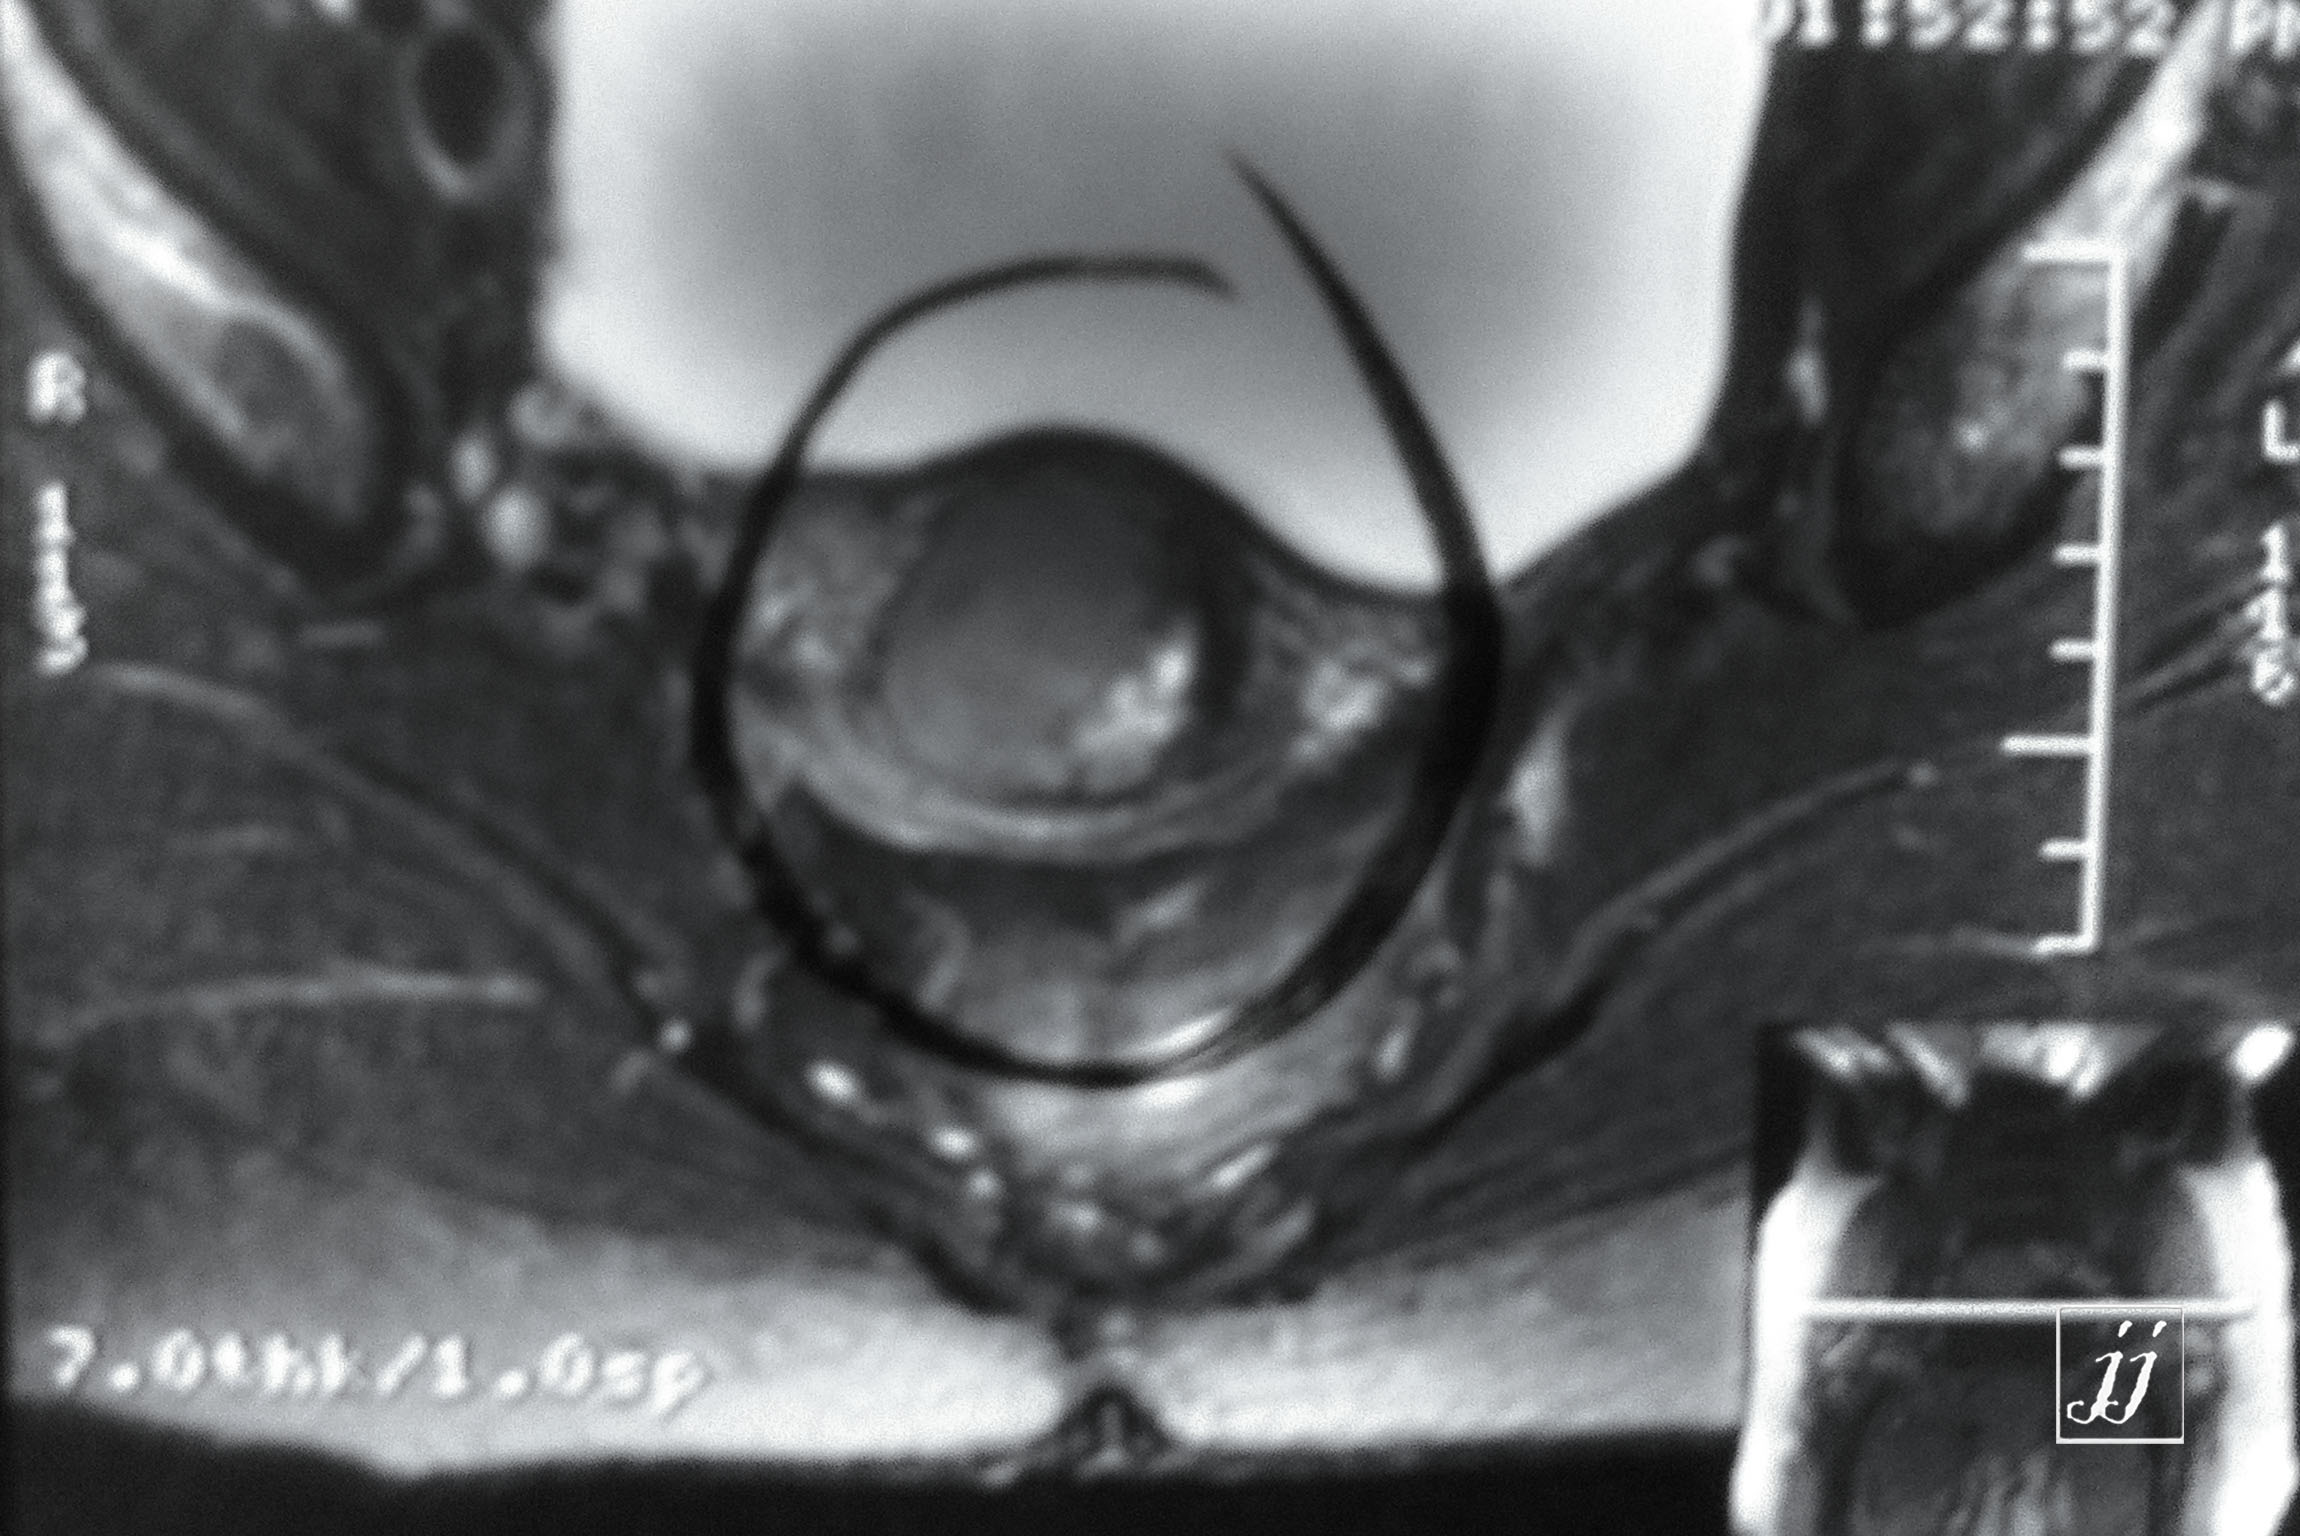

Abdomen- mass lesion posterior to UB and uterus location (4)